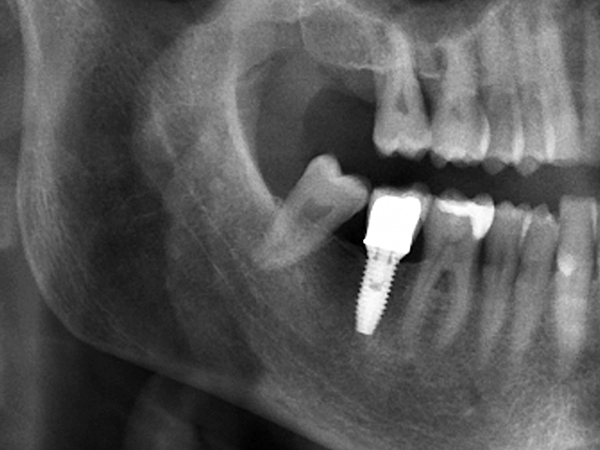

[임플란트] 타치과 임플란트 실패 후 재식립 사례

씹을 때 임플란트가 흔들리거나, 엑스레이 상에서 뼈가 많이 녹아 있는 것이 확인될 때에도 추가 치료 또는 재수술이 필요할 수 있습니다.